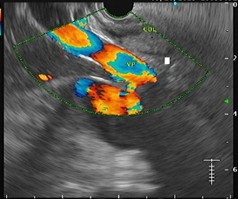

O que é a Ecoendoscopia Alta?

A ecoendoscopia alta, também chamada de ultrassonografia endoscópica do trato digestivo alto, é um exame diagnóstico que associa a endoscopia com a tecnologia do ultrassom. O procedimento permite uma visualização detalhada das camadas da parede do tubo digestivo superior (esôfago, estômago e duodeno) e de estruturas vizinhas, como linfonodos, pâncreas, vias biliares e grandes vasos.

Para que serve a Ecoendoscopia Alta?

A ecoendoscopia alta é indicada na investigação de tumores no esôfago, estômago, pâncreas e vias biliares, além da avaliação de linfonodos aumentados e lesões subepiteliais. Também é útil para estadiamento de câncer e para orientar punções por agulha fina (PAAF) de massas ou linfonodos suspeitos.

Qual o tempo de duração da Ecoendoscopia Alta?

O exame dura em média de 30 a 60 minutos, podendo variar conforme a complexidade do caso e a necessidade de procedimentos complementares, como biópsias.

Quais os cuidados após a Ecoendoscopia Alta?

Após o exame, o paciente permanece em observação até o efeito da sedação passar. É comum sentir um leve desconforto na garganta. A alimentação deve ser retomada apenas após a liberação médica, geralmente algumas horas depois. Acompanhamento é necessário, pois não se deve dirigir após a sedação.

A Ecoendoscopia Alta causa dor?

Não. O exame é feito com sedação, o que garante conforto e ausência de dor durante o procedimento. Após o exame, pode haver leve irritação na garganta, mas sem dor significativa.

Preparativos para o exame

O preparo consiste em jejum absoluto de 6 a 8 horas antes do exame. É fundamental informar ao médico sobre o uso de medicamentos, principalmente anticoagulantes, e sobre condições clínicas prévias como alergias ou doenças cardíacas.